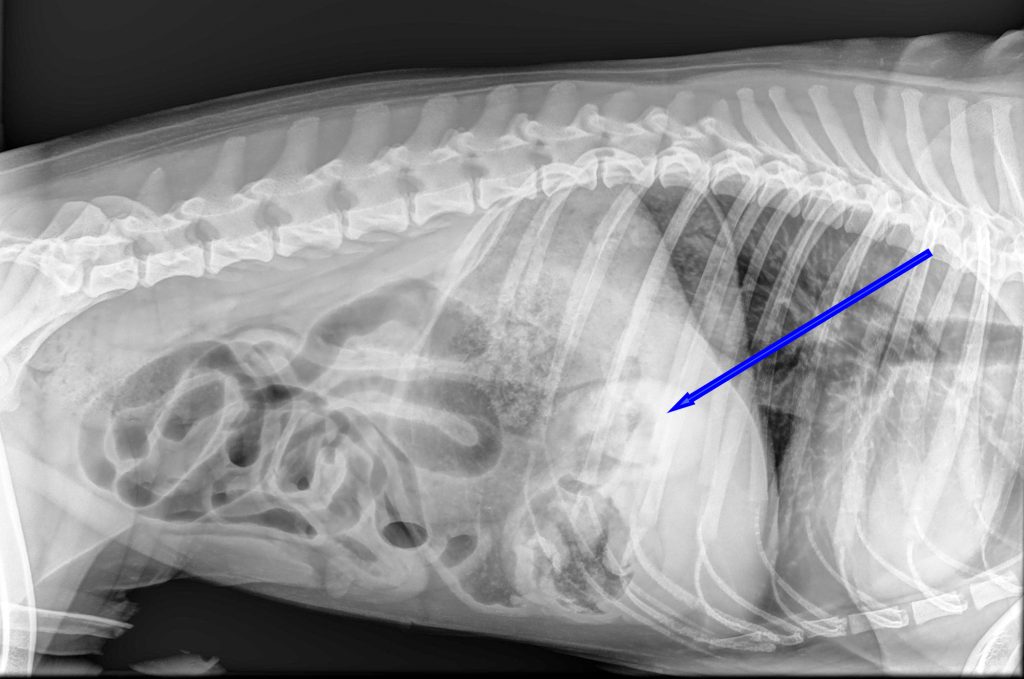

Bij het algemeen onderzoek was de buik gevoelig bij het navoelen en er leek veel gasvorming aanwezig te zijn. Op de röntgenfoto was er een grote maag met veel vulling zichtbaar, waarbij er ook een soort buisvormige structuur aanwezig leek te zijn. Het leek er dus op dat er een vreemd voorwerp in de maag zat. Aangezien Joep al meerdere keren had gebraakt zonder dat er iets uit kwam, was het advies om dit voorwerp operatief te verwijderen.